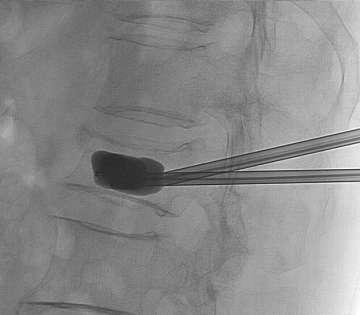

During the procedure, the patient is lightly sedated and lies on their tummy. Under x-ray guidance, we place the needle into the vertebral body (Figure 2). Unlike most pain services where a relatively simple portable C-arm X-ray machine is used, we use the state-of-the-art biplane neuro-angiosuite, which is capable of 3-D navigation in the brain and spine (Figure 3). In rare occasions, placement of the needle is challenging due to previous implantation of metal hardware that obscures the normal bony landmarks, or due to severe osteoporosis. The 3-D navigation capability provides us with the ability to very accurately place the needle without relying on the classic radiological bony landmarks (Figure 4).